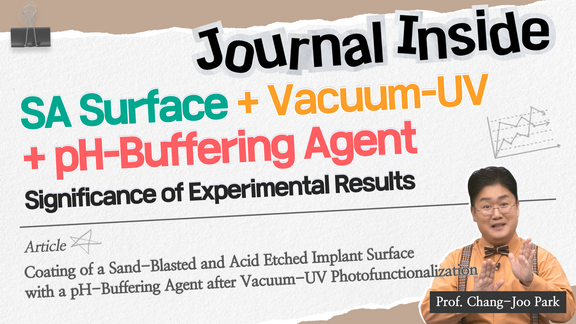

Coating of a Sand-Blasted and Acid-Etched Implant Surface...

Journal Inside

2023-12-14T00:00